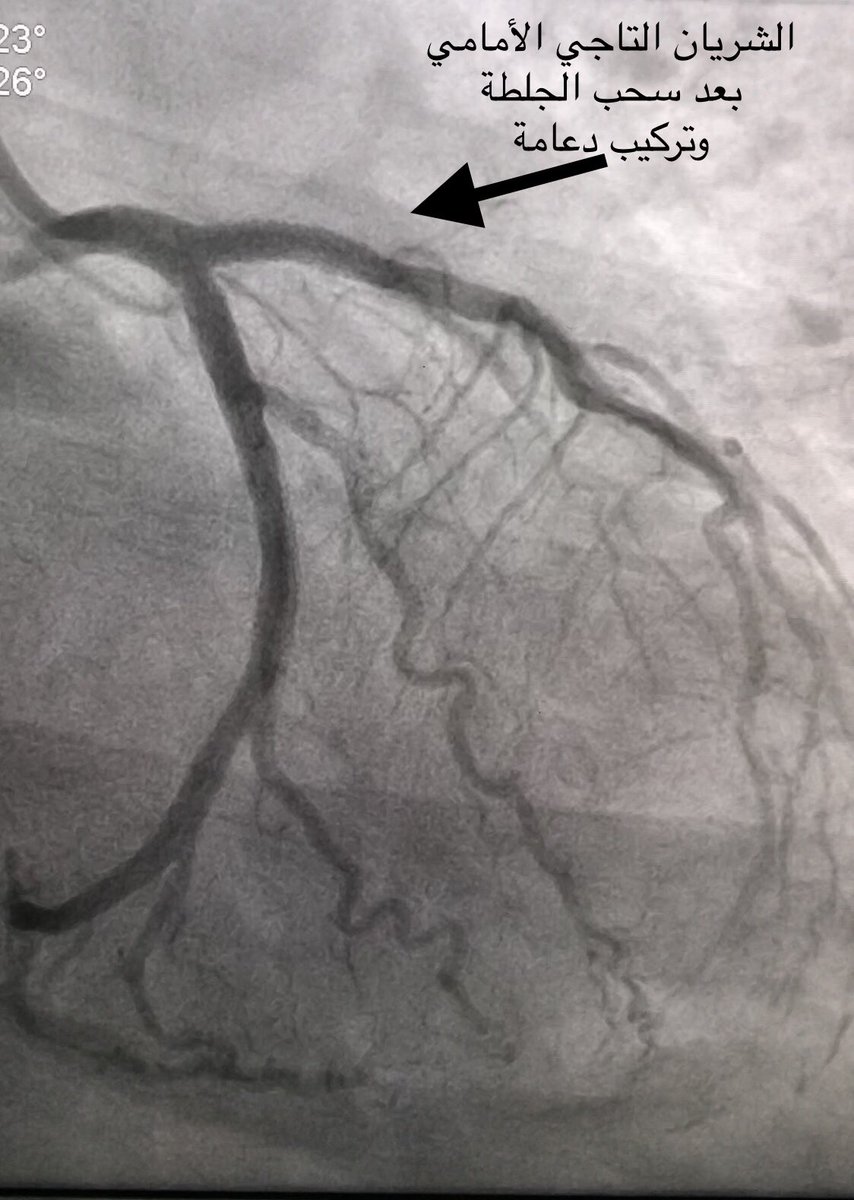

بينت القسطرة انسداد كامل بالشريان التاجي الأمامي

وتم علاجها بنجاح